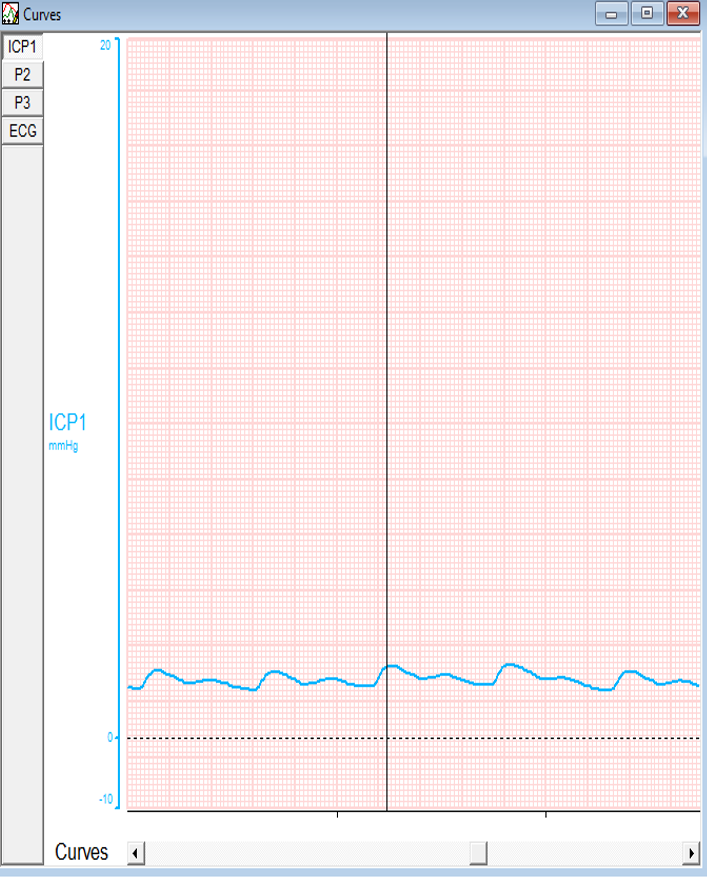

As durotomy is done, both ICP and ICP A again plummet to the normal values, also evidenced by the graph.